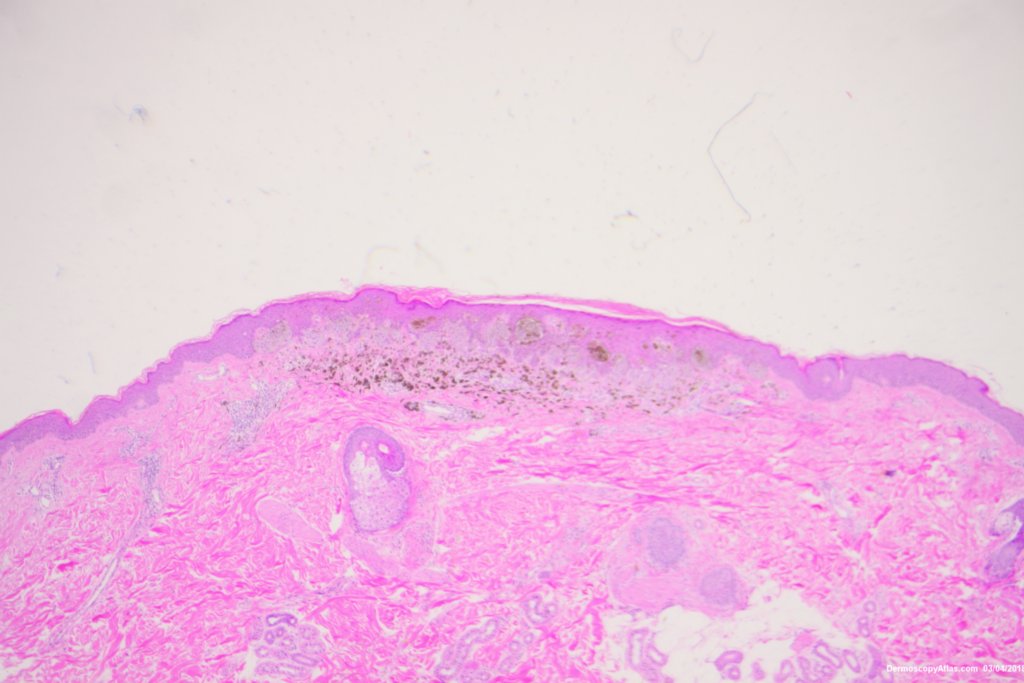

Diagnosis: Reed nevus

Sudden onset of a new pigmented lesion on the shoulder. Dermatoscopy shows an actively proliferating lesion with peripheral pseudopods that involve most of the circumference. Clinically this was either a Reed nevus or a Spitzoid melanoma. The histology favours a Reed nevus.